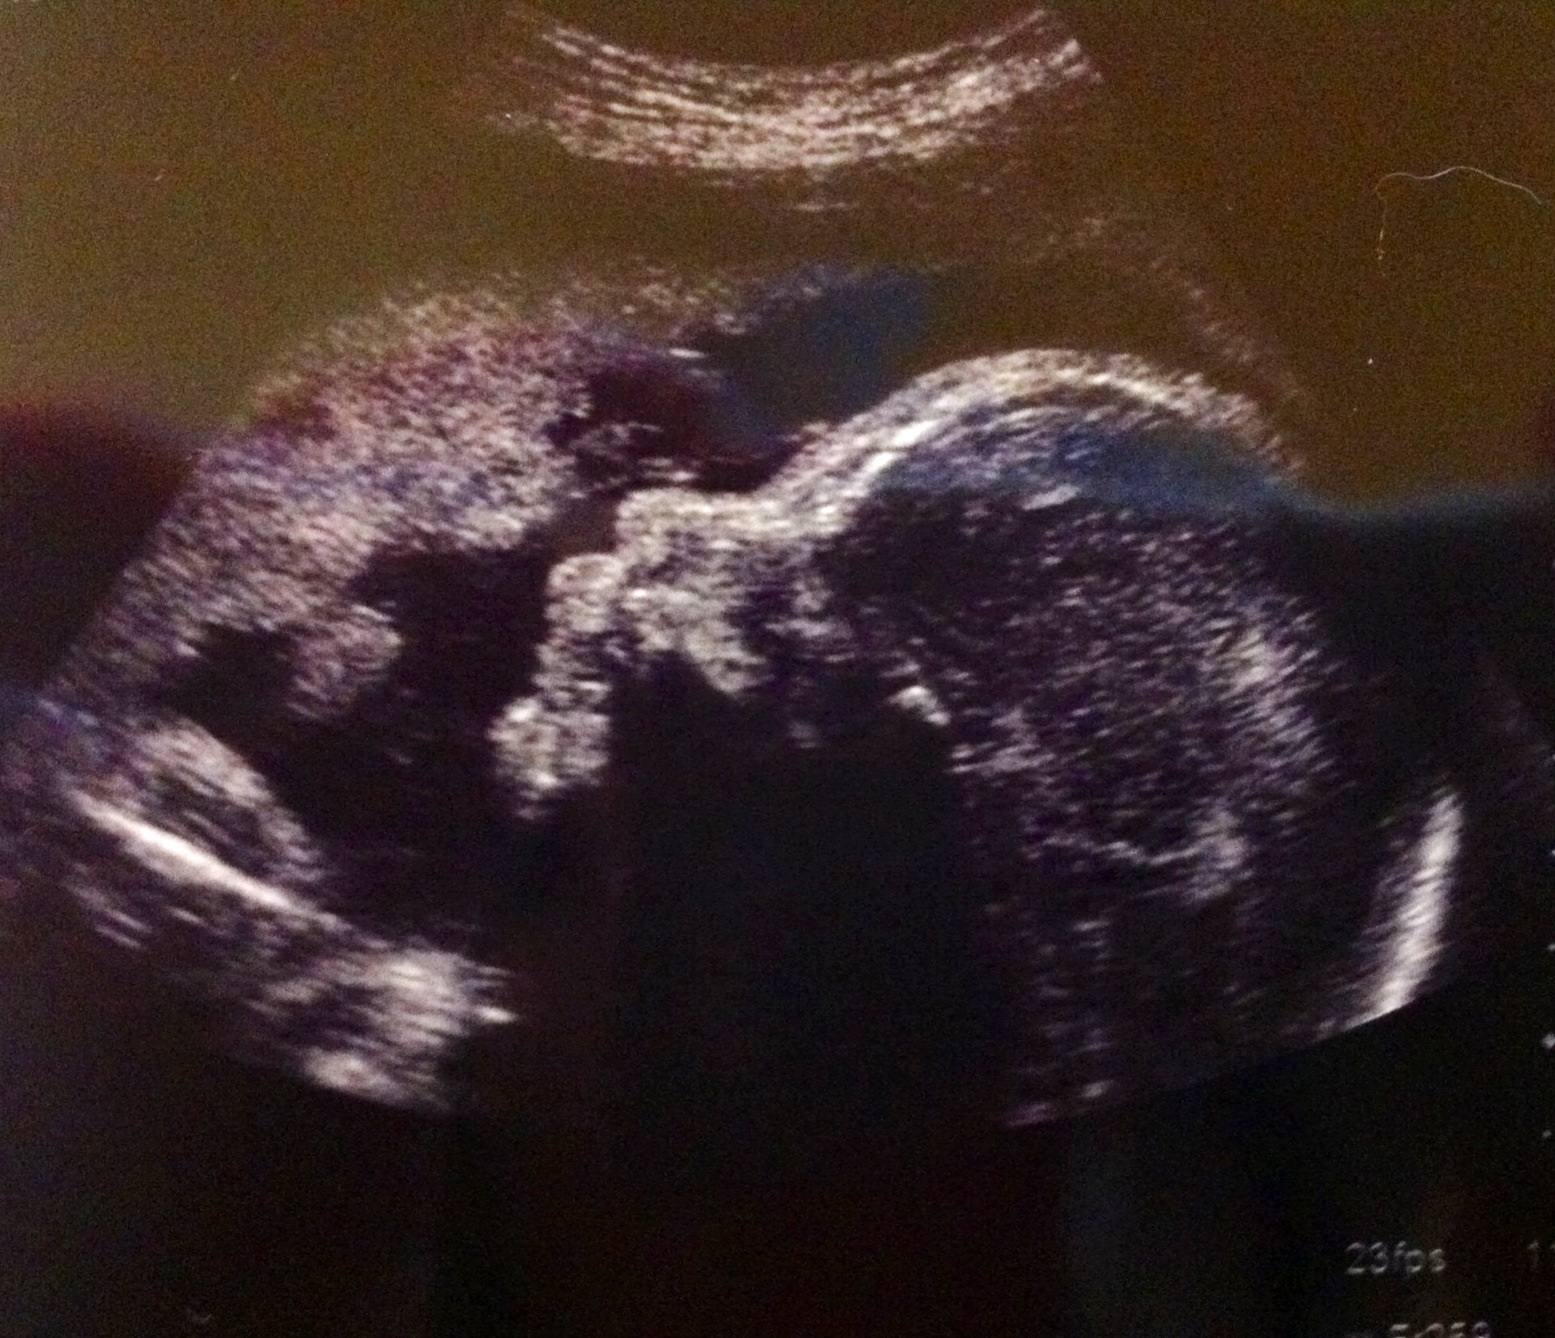

My girls are getting big and strong!! We visited the perinatologist yesterday morning (you know, with the 52 inch sonogram monitor) and walked out with a good report on both momma and baby. They both are measuring identically at 2 pounds, 10 ounces. Jolie is actually about 6 grams bigger than Parker, which was such a surprise since she has been much smaller than Parker from the very beginning. Either way, I have 5 pound of baby to carry..err.. lay around! Heart beats were 150 bpm and 153 bpm.. and both, of course, were awake and active (per their usual)

We attempted to try for a couple of 4D images..but Parker had her foot in Jolie’s face (even in separate sacs they are all over each other.) and her own hand in front of her own face. Difficult babies. We go back in a couple weeks and will try again for another. So, we settled for a couple of the 2D for today.

Jolie Grace

Parker Jane